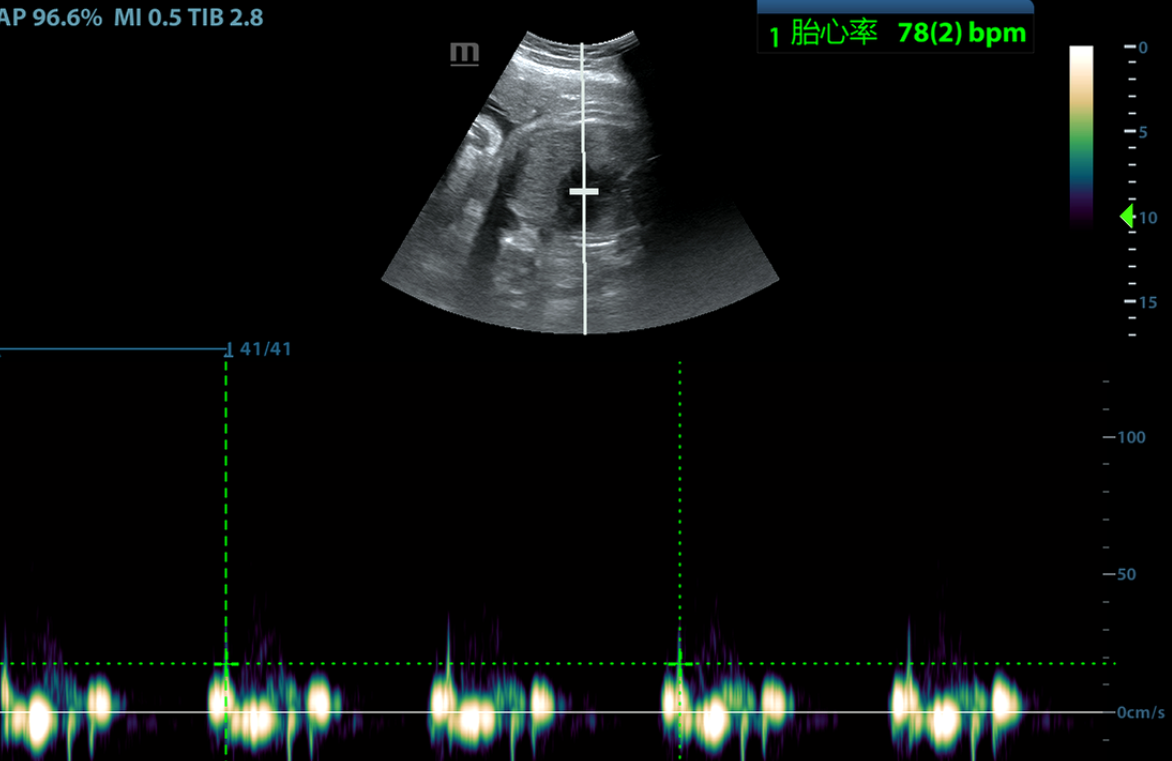

超声检查基本排除了胆囊炎及胆结石导致的疼痛,且发现盆腹腔大量积液。就在救治准备工作即将完成之际,婴儿的胎心因为母亲的失血突然不稳定,出现了严重的胎心率下降,胎儿宫内窘迫,孕妇的生命体征逐渐失去稳定。救治团队核心专家立刻给出诊断:子宫破裂的诊断基本明确,且腹腔存在活动性内出血,需要启动紧急剖宫产。